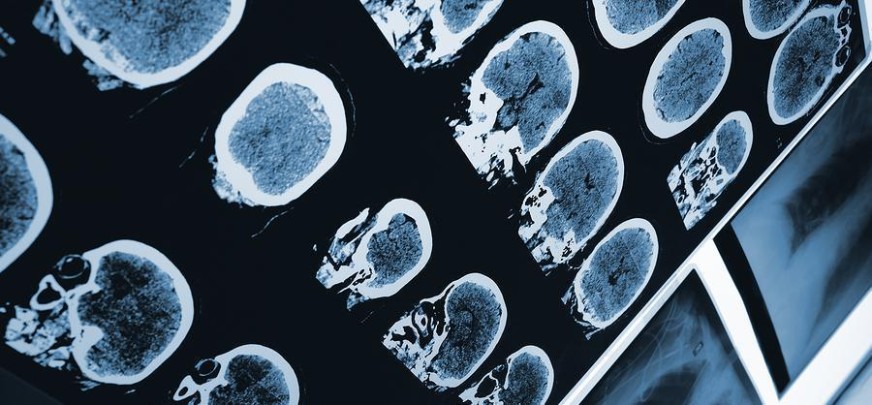

There are a number of scans that are used in cancer detection, both for diagnosis and for tracking through the treatment process. Some of these scans can be quite expensive, and some carry health risks of their own, so they are prescribed judiciously. Scanning technology commonly used in cancer detection includes mammography, CT scans, ultrasounds, PET scans, and even X-rays. Cancer-detection technology helps to locate and map growths and tumors, or areas where sufficient cancer cells have combined to form a mass.